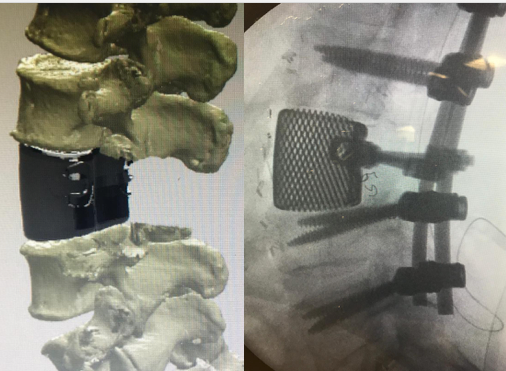

Il primo impianto in Toscana di una vertebra stampata in 3D è stato eseguito con successo nelle scorse settimane a Pisa, nell’Unità operativa di Ortopedia e traumatologia 2 dell’Aoup diretta dal professor Rodolfo Capanna. Il paziente è un uomo di 56 anni, affetto da una neoplasia primitiva ossea che interessava la terza vertebra lombare, in trattamento nel reparto di Oncologia dell’ospedale di Prato. Dopo un esame bioptico, che aveva confermato la malignità della lesione, è stato pianificato un intervento chirurgico di resezione in blocco della vertebra L3 affetta dal tumore e di ricostruzione della stessa mediante una nuova vertebra, stampata in titanio in 3D, ottenuta dalla rielaborazione e ricostruzione dell’esame Tac del paziente.

L’impianto utilizzato é stato sviluppato specificamente per questo paziente partendo dalle immagini tac della sua colonna vertebrale, che sono state ricostruite tridimensionalmente per poter ottimizzare il disegno dell’impianto. La collaborazione dei chirurghi con gli ingegneri dell’ITC (Instituto Tecnológico de Canarias) ha portato al disegno di un impianto perfettamente congruente alla resezione in blocco pianificata in fase preoperatoria. Il design è stato ottimizzato in modo da ottenere le condizioni biomeccaniche (elasticità e resistenza) più adatte a favorire la sua colonizzazione da parte del tessuto osseo del paziente; a tal fine a struttura dell’impianto ha una porosità di circa il 90 % per lasciare spazio libero, che sarà occupato dall’osso di nuova generazione. L’impianto è stato realizzato con una stampante tridimensionale partendo da polvere di titanio grado 23.

L’intervento chirurgico, durato 13 ore, è stato eseguito mediante un doppio approccio chirurgico posteriore ed anterolaterale, e vi ha preso parte un’equipe multidisciplinare composta da: professor Paolo Parchi, associato all’Università di Pisa, dottor Simone Colangeli, dottoressa Sara Stagnari (chirurghi ortopedici); dottor Alessandro Gasbarrini (chirurgo ortopedico, direttore dell’Unità operativa di Chirurgia vertebrale oncologica e degenerativa all’Istituto ortopedico Rizzoli, ideatore della metodica come consulente esterno); dottor Daniele Adami e dottor Michele Leo (chirurghi vascolari); dottoressa Silvia Nardi, dottoressa Elisa Dimitri, dottor Leonardo Santini, dottoressa Elisa Bulleri (anestesisti e rianimatori); Andrea Meini, Francesca Pellicci, Lisa Lodovichi, Barbara Carmignani, Valerio Lupi (strumentisti ed infermieri di sala operatoria); Marzia Frangioni, Sabrina Micheletti (infermieri addetti all’anestesia); Alfredo Orsi, Francesco Maenza, Agusto Micheli (tecnici di radiologia sanitaria); Marco Cini (infermiere di sala gessi). Durante la degenza il paziente ha ripreso la deambulazione assistita ed è stato dimesso in buone condizioni il 14° giorno post-operazione.